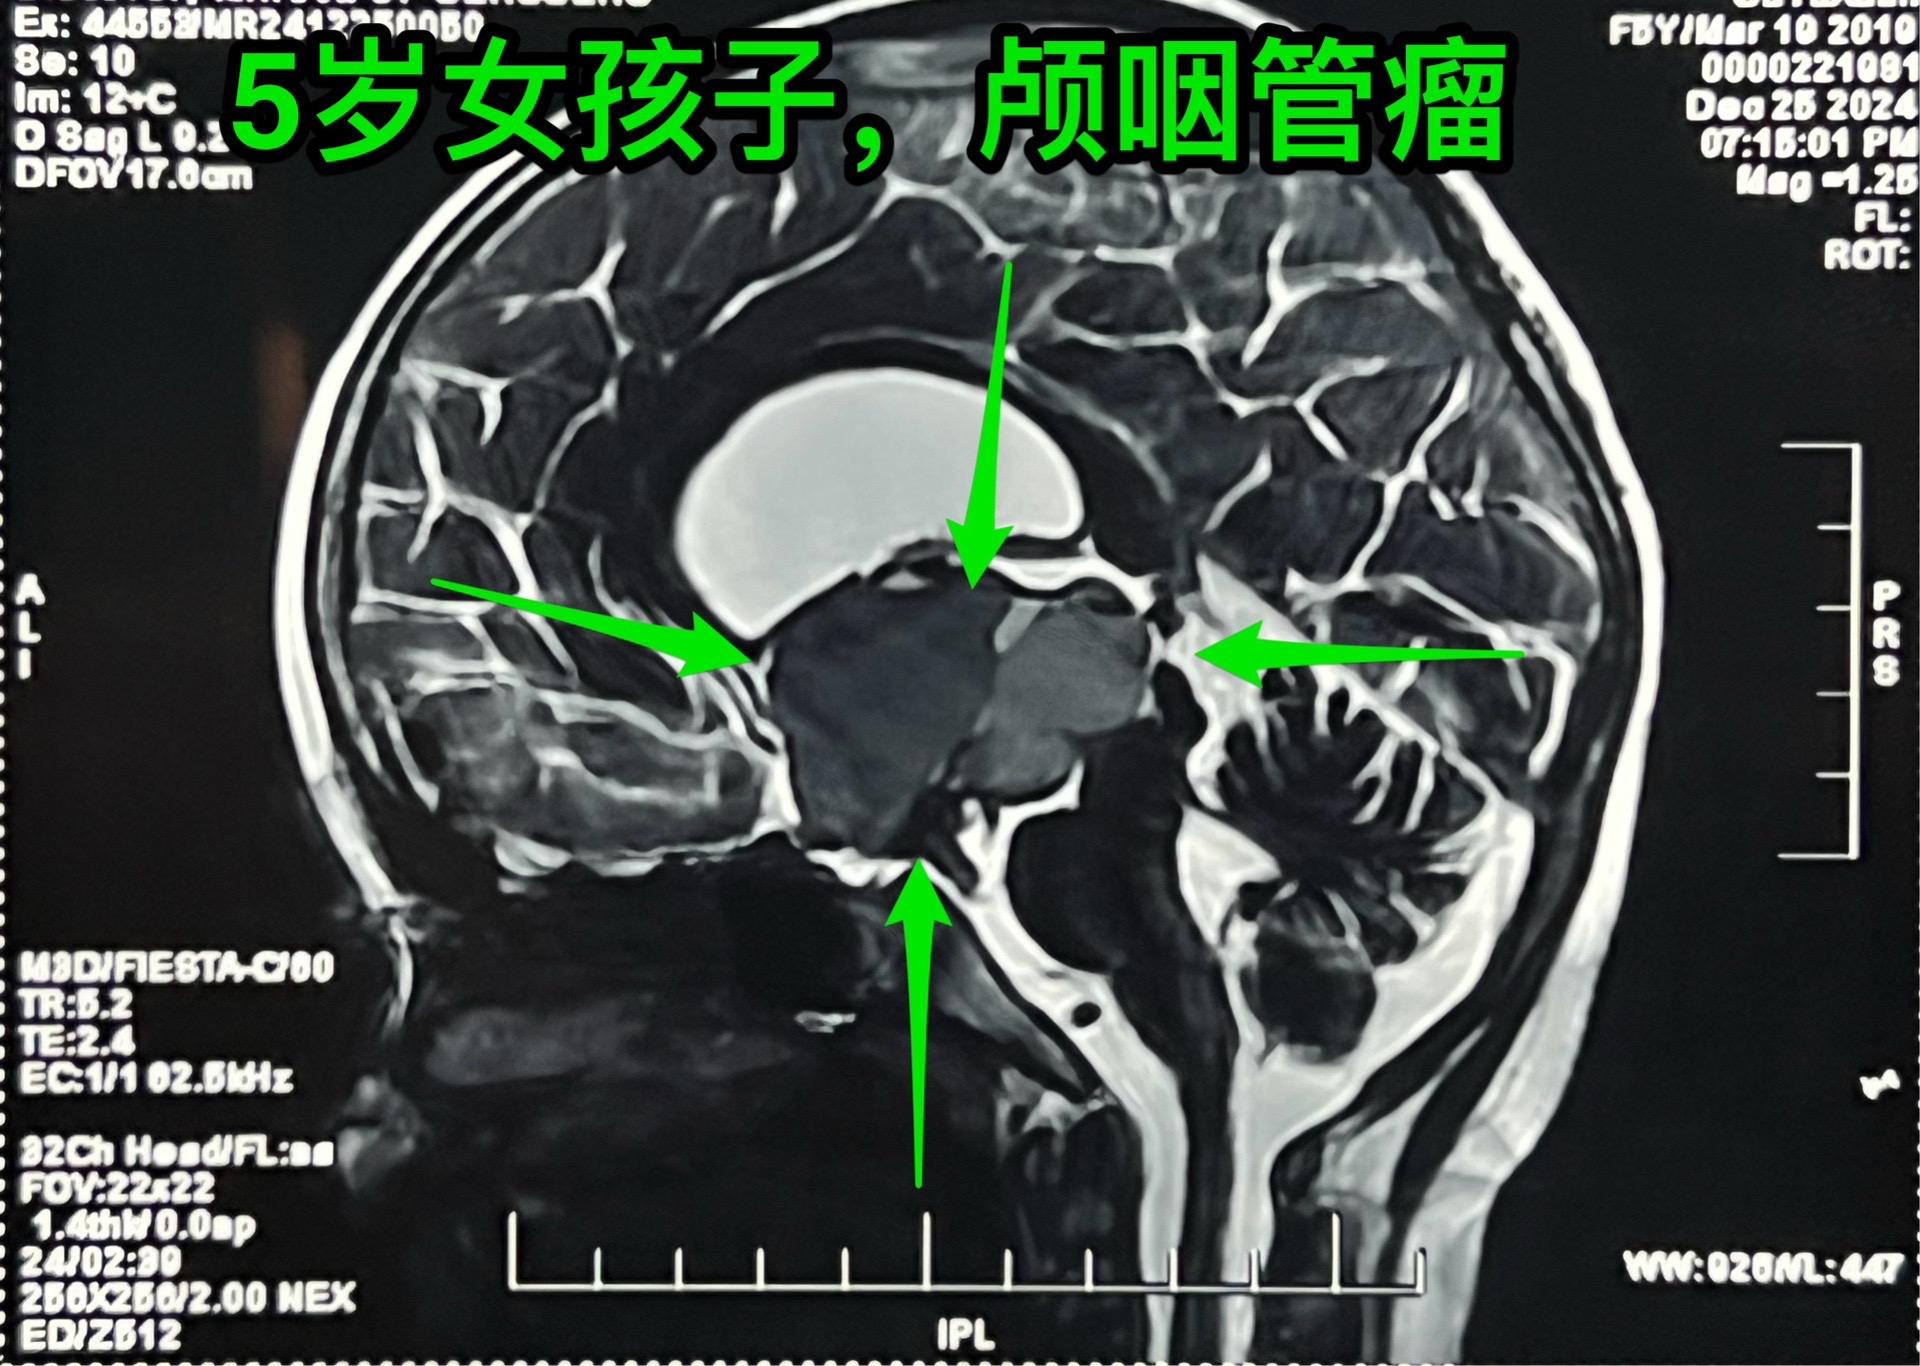

五岁商丘女孩颅咽管瘤像鸡蛋大。女孩子因为反复头痛、呕吐起病,一开始怀疑是胃肠炎,治疗后效果不好。于2024年12月18日作脑部磁共振和CT发现脑部肿瘤,怀疑是颅咽管瘤,孩子的妈妈和我加了,说肿瘤像鸡蛋那么大,焦急万分。 小孩子几经周折,最终到三博脑科医院找我办理住院手续。刚刚住院后又患感冒,发烧、咳嗽。感冒治好之后才于2025月1月7日作了手术。手术很顺利。 这个肿瘤体积大,导致脑积水,主体位于第三脑室内。对于我们科来说,这样的手术还不算是最难的。 希望小